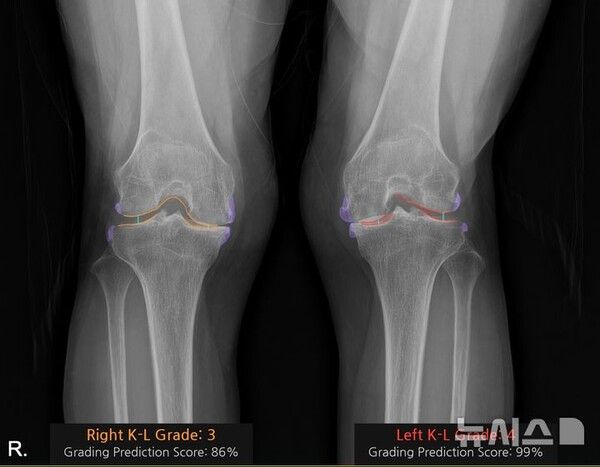

뉴시스 보도에 따르면, 양쪽 무릎 수술을 고려했던 박씨는 왼쪽 무릎에서 관절 사이의 협착과 큰 골극, 심한 뼈 변형을 확인하고 의료진과 상의 끝에 동시 수술보다는 수술이 더 시급한 우선 왼쪽 무릎을 먼저 수술하기로 했다.

박씨는 "무릎 사진을 찍었는데 닳은 부위를 색깔로 구분해 보여주니 왼쪽 무릎 상태가 더 안좋은 게 바로 이해가 됐다"며 "세상이 점점 좋아진다"고 말했다.

식품의약품안전처로부터 의료기기 사용허가를 받은 '코네보 코아'는 환자의 무릎 엑스레이(X-ray) 영상을 10초 만에 분석해 K-L(Kellgren–Lawrence) 등급별색상으로 관절염의 심각도를 직관적으로 시각화한다. 화면에는 손상 부위의 골극(뼈 돌기)과 관절 간격이 색상으로 표시돼, 환자 본인도 상태를 한눈에 이해할 수 있다.

'코네보 코아'는 단순한 이미지 분석이 아니라, 관절 간격·골극 형태·연골 손상 패턴을 학습한 AI가 진단 기준에 맞춰 자동 분류하는 구조다. 초기 단계(Grade 0~1)까지도 판정 보조가 가능해 관절염의 조기 발견에 도움을 준다.

또 의료진이 일일이 주관적으로 평가하던 K-L 등급 판정의 일관성을 높여주고 판독 편차를 줄이는 데 기여한다.